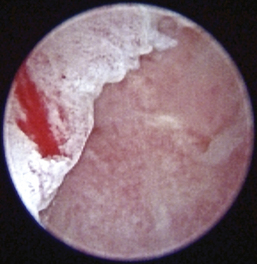

image

Figure 20-9 Bulging pars flaccida in a dog without otitis media. 1, Pars flaccida; C, caudal; D, dorsal; R, rostral; V, ventral.

(Courtesy of Dr. Lynette Cole, The Ohio State University, Columbus, Ohio.)

Figure 20-10 Bulging pars flaccida in a Cavalier King Charles spaniel dog with primary secretory otitis media. 1, Pars flaccida.